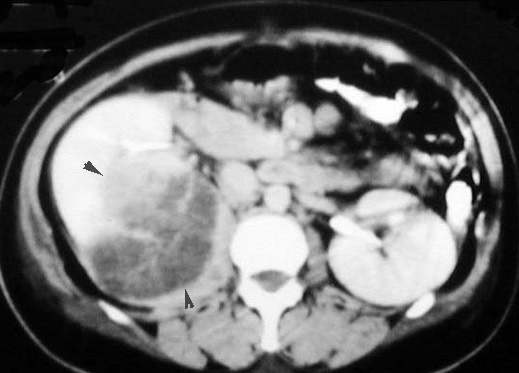

CT scan in a patient with Renal Cell Carcinoma

• Arrow points to solid hypo dense mass in left kidney .

• Arrowheads pointing to normal parenchymal enhancement.